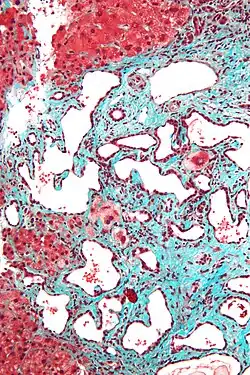

Micrograph of a bile duct hamartoma. Trichrome stain. Intermediate magnification -

Histopathology of a bile duct hamartoma, high magnification, H&E stain. It shows typical features of bile duct hamartoma: Small to medium sized, irregularly shaped bile ducts lined by bland cuboidal epithelium (may also be flattened). Prominent intervening collagenous stroma. Bile ducts containing eosinophilic debris (may also contain inspissated bile) -